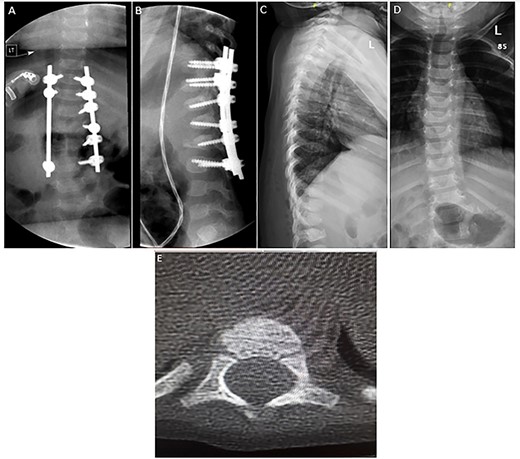

The decision was to perform posterior thoracolumbar instrumentation. The risks and possible complications of the surgery were explained to the family. The aim of the surgery was to correct the kyphotic deformity and facilitate the rehabilitation and nursing course. Posterior thoracolumbar instrumentation using the posterior cervical fixation set was successfully performed (Fig. 4A and B). In the surgery, the facet joint was preserved to prevent fusion and long-term sequelae such as crankshaft deformity. The patient recovered well with no complications after the surgery and was discharged home on a TLSO brace.

(A–B) Spine radiograph demonstrating bilateral paraspinal rods spanning from the level of T10 to L3 transfixed with pedicular screws. The screws and rods are in situ with signs of healed fracture. (C–D) Interval removal of the hardware transfixing the compression fractures of the lower thoracic and upper lumbar vertebrae. (E) Axial CT scan 7 months postoperatively confirming fusion.

Outcome and follow-up

Seven months after the surgery, a follow-up CT and plain radiograph showed healing of the fracture and excellent alignment. The hardware of the posterior thoracolumbar fixation was removed to prevent scoliosis and crankshaft deformity (Fig. 4C–E). The patient tolerated the procedure well and was discharged with regular clinical and radiological follow-up in the pediatric neurosurgery clinic. Her neurological status remained unchanged, i.e. ASIA A.